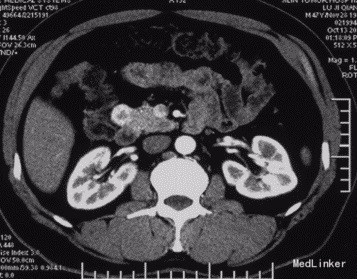

查体:神清,腹软,未及包块,无压痛及反跳痛,神经系统检查未见异常 辅查:外院头颅CT平扫:腔隙性脑梗;胰腺CT平扫:胰头、十二指肠降部稍低密度影,肝内多发小囊肿;上腹部增强CT:胰腺低密度影,考虑良性;肝内多发小囊肿。 入院检查:血、尿、粪常规、肝肾功能、电解质、凝血功能正常;AFP、CEA、CA19-9、CA125、CA15-3、CA72-4均正常;胰岛素78.33mIU/L,C肽 4.91ug/L。腹腔动脉DSA:胰头区富血供肿瘤; 胰腺增强MRI:1、胰头部富血供病变,考虑胰岛素瘤可能性大;2、肝内多发小囊肿。

术前诊断:1、胰头占位性病变(胰岛素瘤?),2、腔隙性脑梗塞,3、肝内多发小囊肿。 术后诊断:1、胰头胰岛素瘤,2、腔隙性脑梗塞,3、肝内多发小囊肿。 入院后控制血糖,完善相关检查在腹腔镜下行胰岛素瘤切除术,术中为、十二指肠、胆囊、横结肠未见异常,胆总管无扩张,打开胃结肠韧带,于胰头健可见大小约2*2cm肿块,表面光滑,边界清,突出于表面,遂行胰岛素瘤切除术超声刀沿肿块边缘完整切除肿块,检查未伤及主胰管。 术后监测血糖,行抗炎、抑酸、补液等对症支持治疗,复查C肽及胰岛素均正常,空腹血糖值正常,康复后出院。